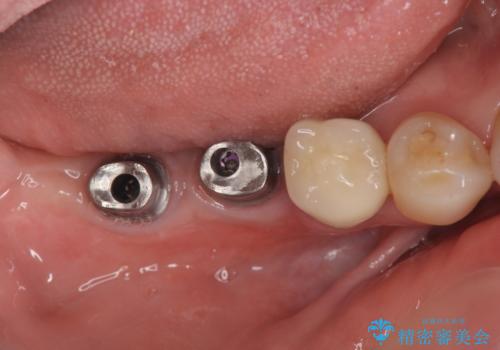

- 「奥歯で噛むと痛い、いつも膿のにおいがして不快、改善してほしい。」と治療を希望され来院されました。

精査した結果、奥歯の根は破折しており抜歯を避けられない状況でした。

咬合力が強く、その他の歯の破折も防ぐために奥歯の咬合機能をインプラントを用いて回復する治療計画を立てます。

- 99万円(インプラント×2・チタンカスタムアバットメント×2・ジルコニアクラウン×2・仮歯×2)費用は治療当時の料金となります